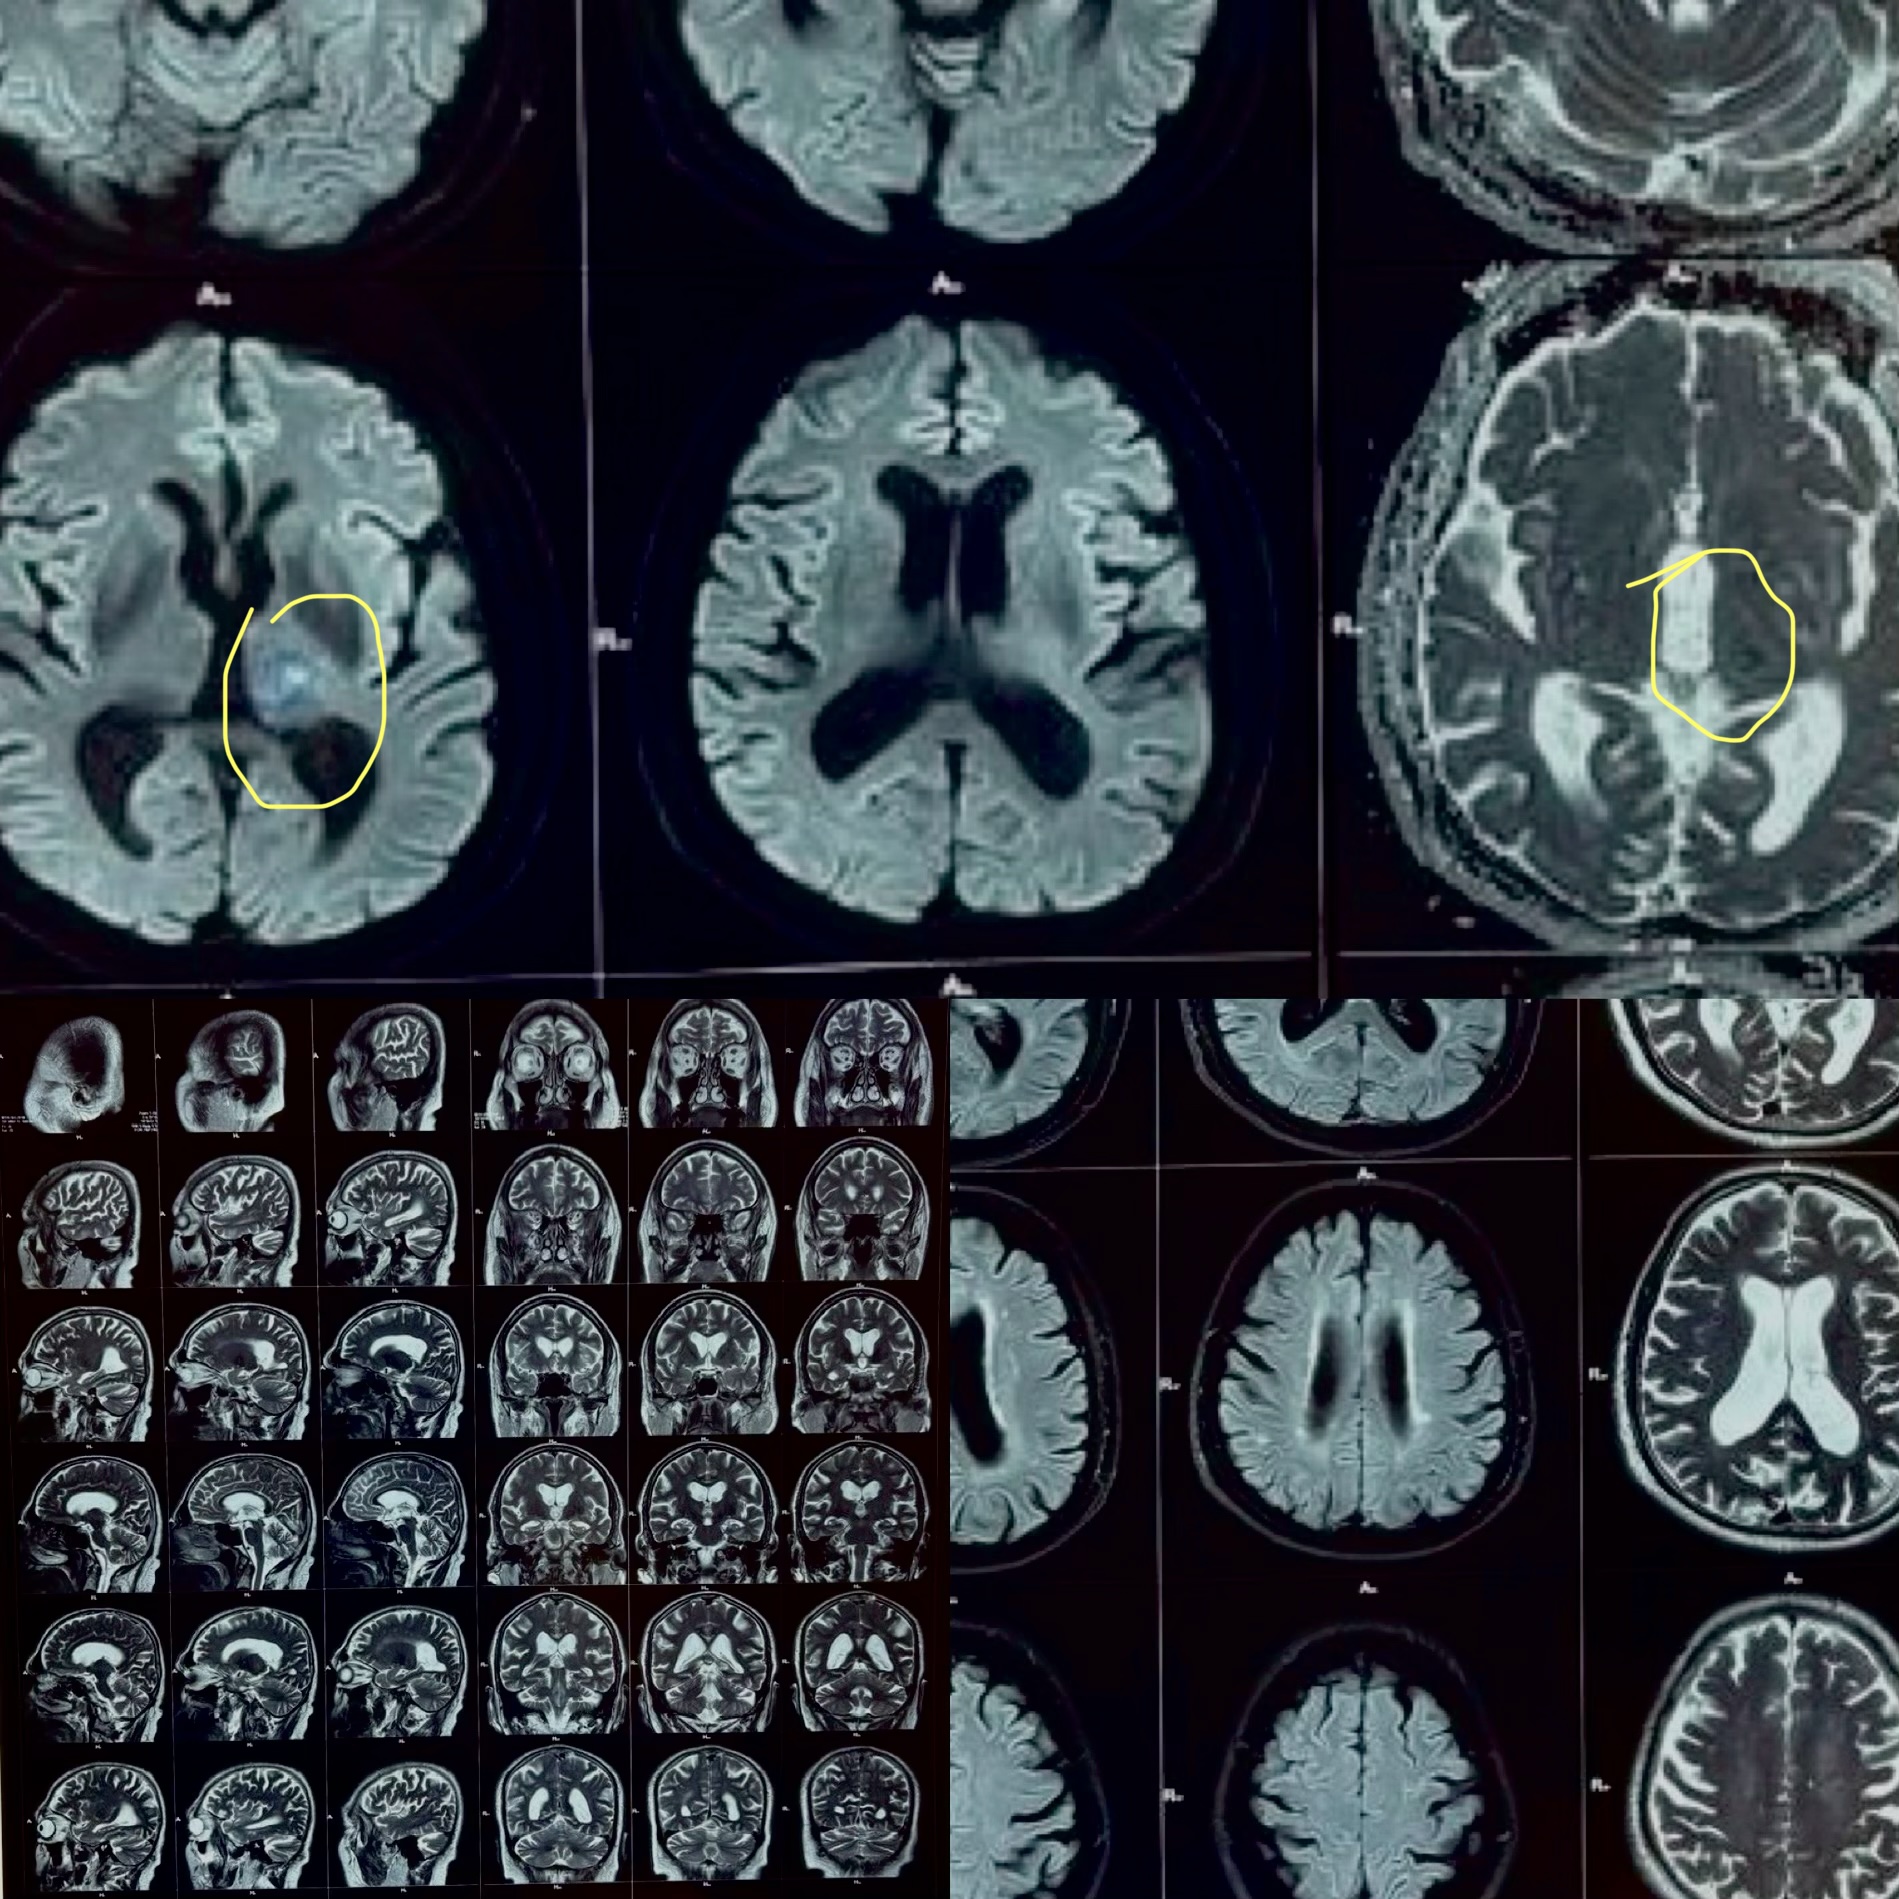

MRI Brain (Mahajan Imaging and Labs, 21 April 2026)

Key Finding: A small, focal area of restricted diffusion in the left thalamus, consistent with an acute ischemic infarct (a tiny area of brain tissue that lost its blood supply and sustained injury, located in the thalamus, the brain's central relay station for sensation and consciousness).

No hemorrhage was identified. No large vessel territory infarction. No mass effect. Ventricular system and basal cisterns appeared normal.

This was the defining finding: the hand numbness was not diabetes-related, not heat-related. It was a thalamic stroke presenting as episodic sensory TIAs before a small completed infarct declared itself.